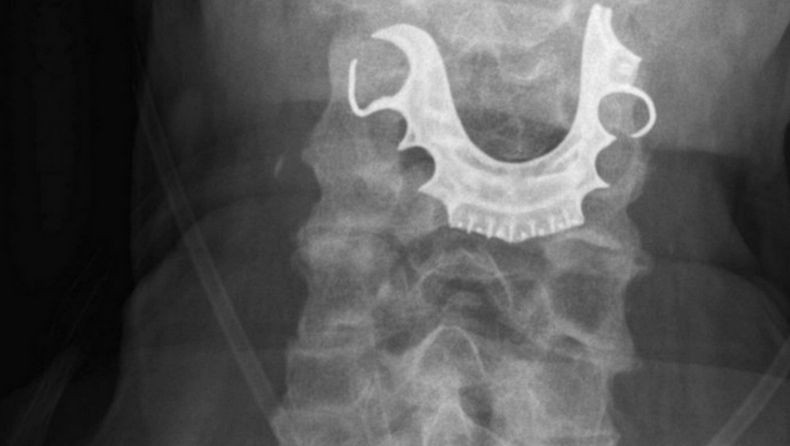

Gigi palsu milik pria Inggris masuk tenggorokan saat menjalani operasi (Foto: AP)

Hasil pemeriksaan menunjukkan, di tenggorokan pria yang tak disebutkan identitasnya itu terdapat gigi palsu serta kawat. Gigi itulah menyumbat saluran di tenggorokan.